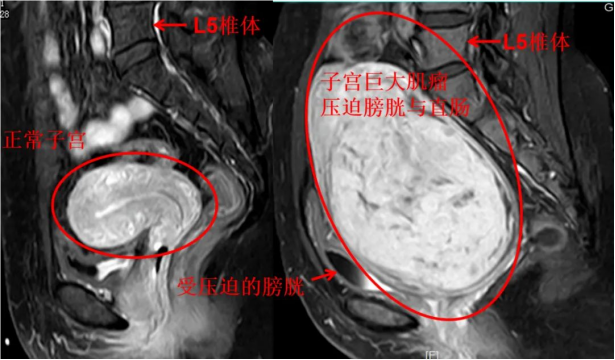

胎儿成像

软组织分辨率较CT更高